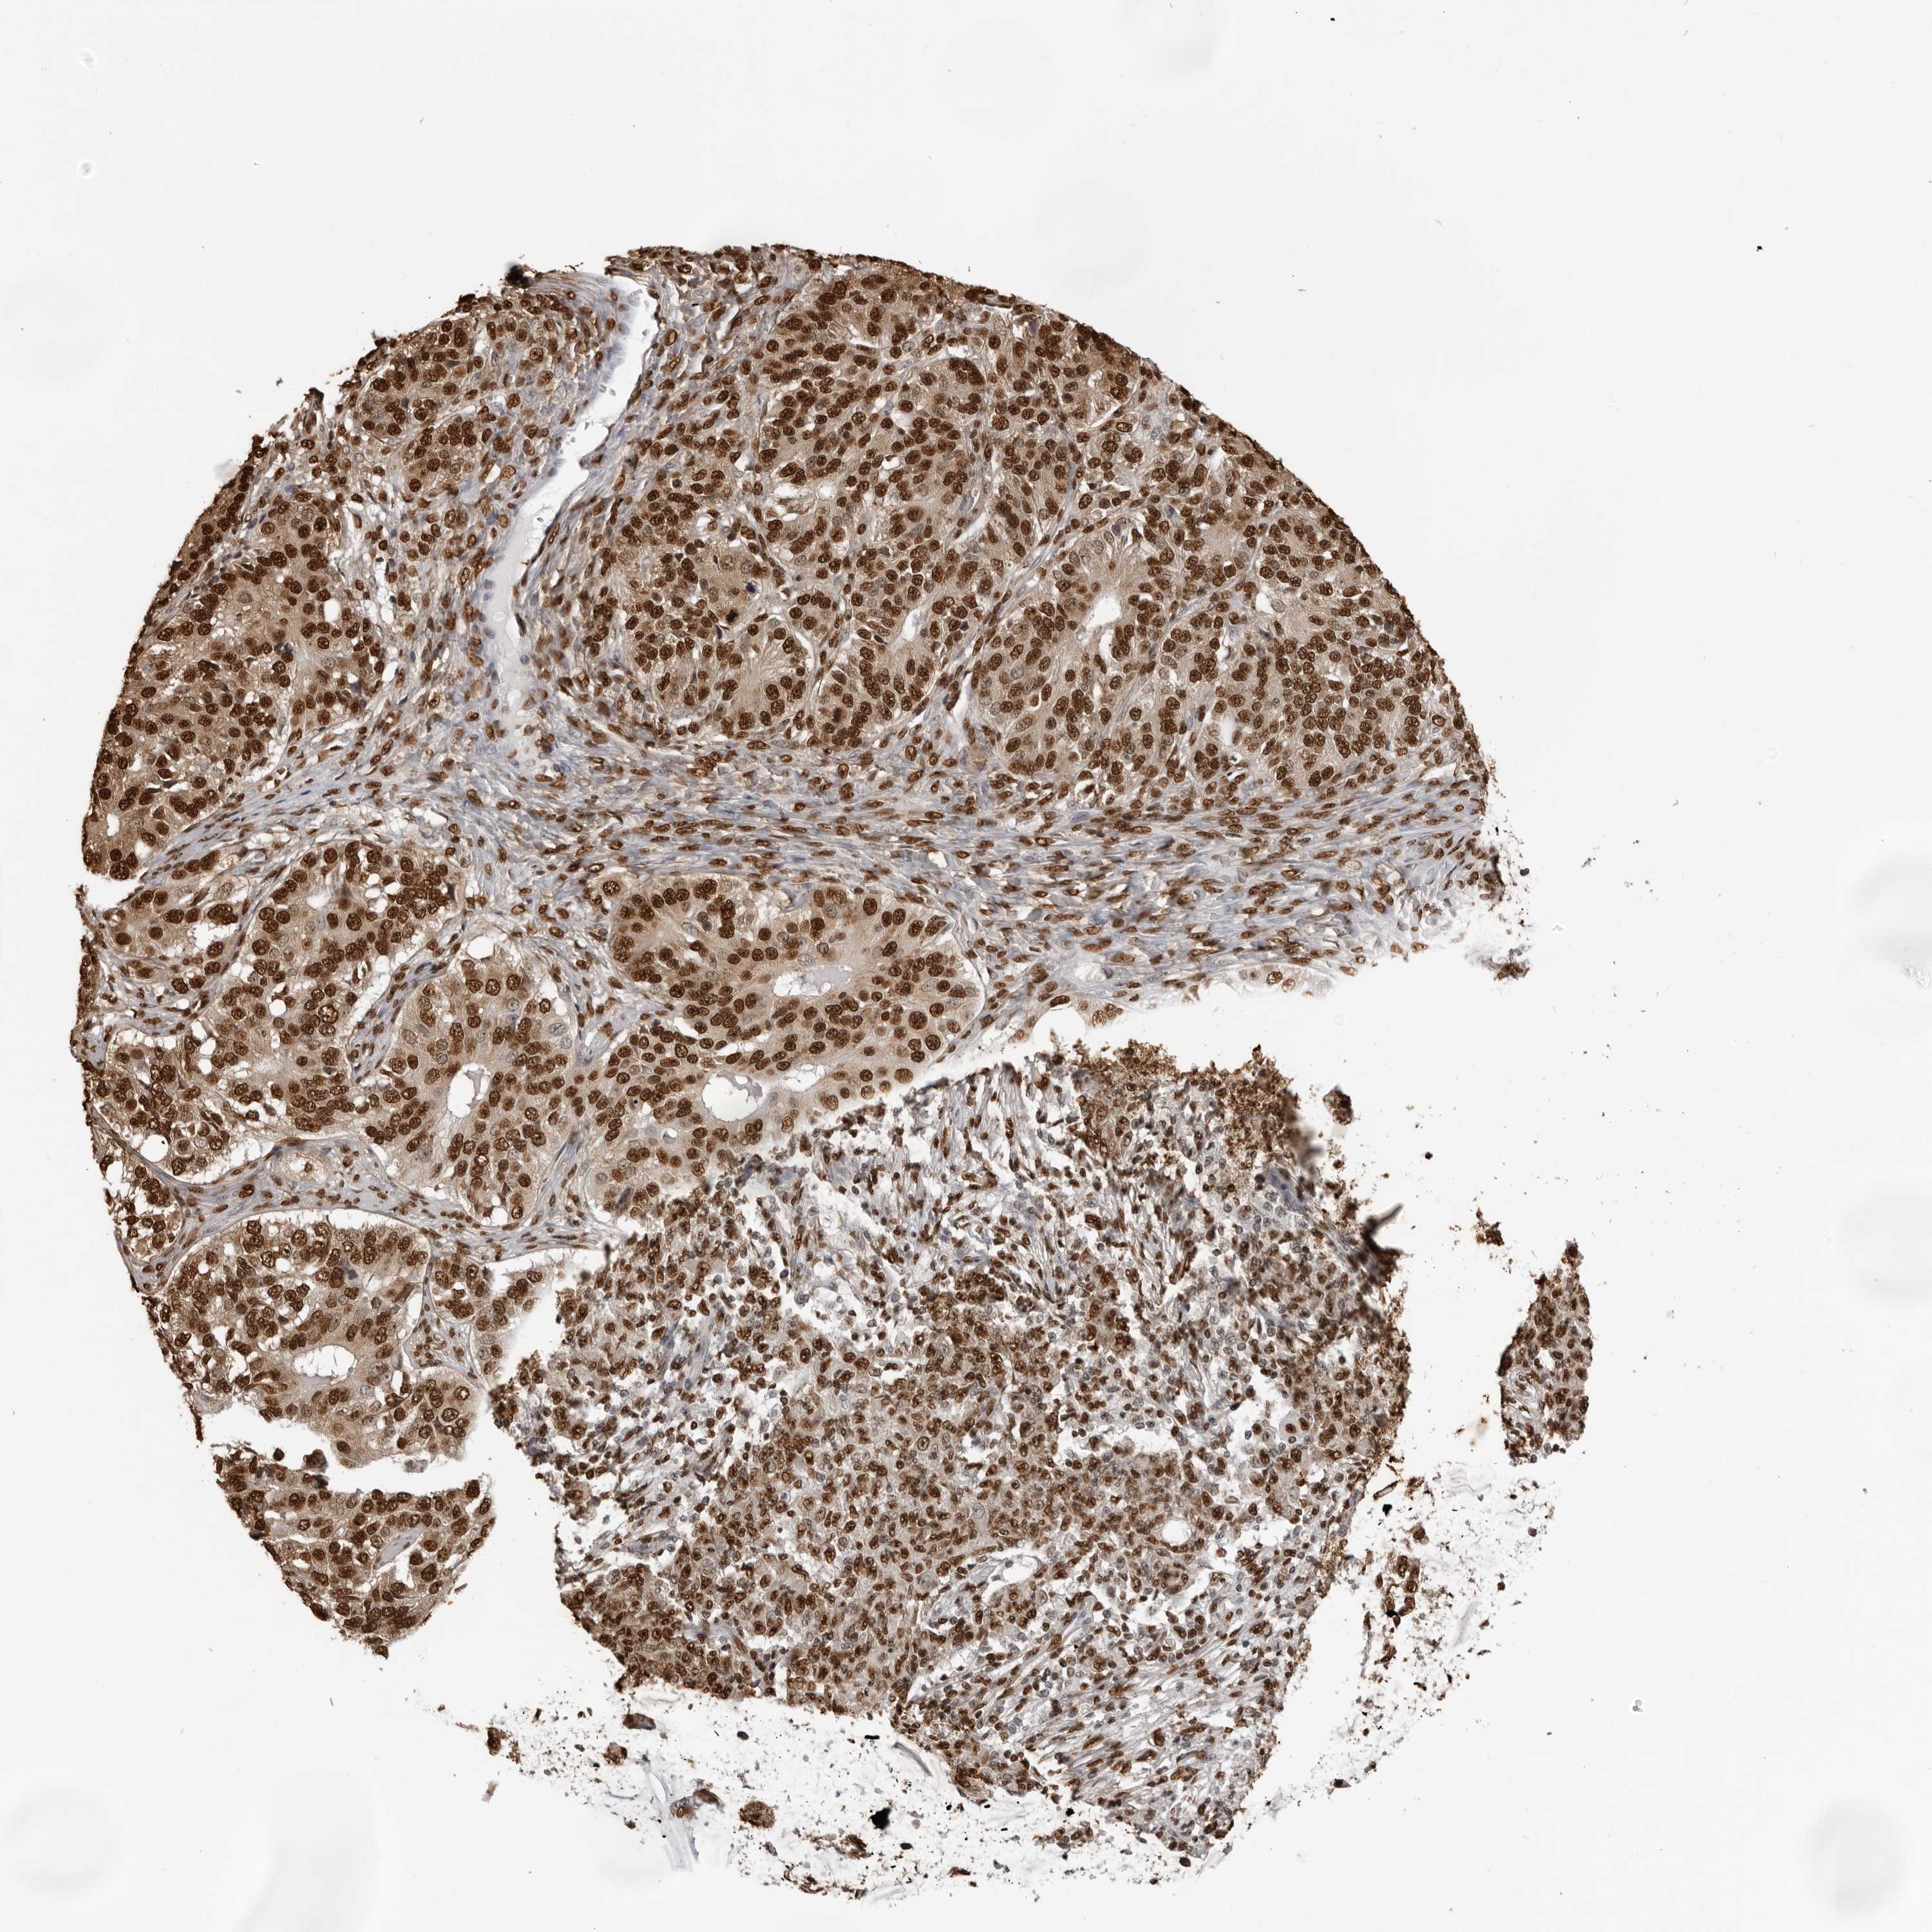

Antibody HPA024037

Staining

High

Medium

Low

Not detected

Intensity

Strong

Moderate

Weak

Negative

Quantity

>75%

75%-25%

<25%

None

Location

Nuclear

Cytoplasmic/membranous

Cytoplasmic/membranous,nuclear

Cystadenocarcinoma, serous, NOS

Carcinoma, endometroid

Cystadenocarcinoma, mucinous, NOS

Carcinoma, NOS